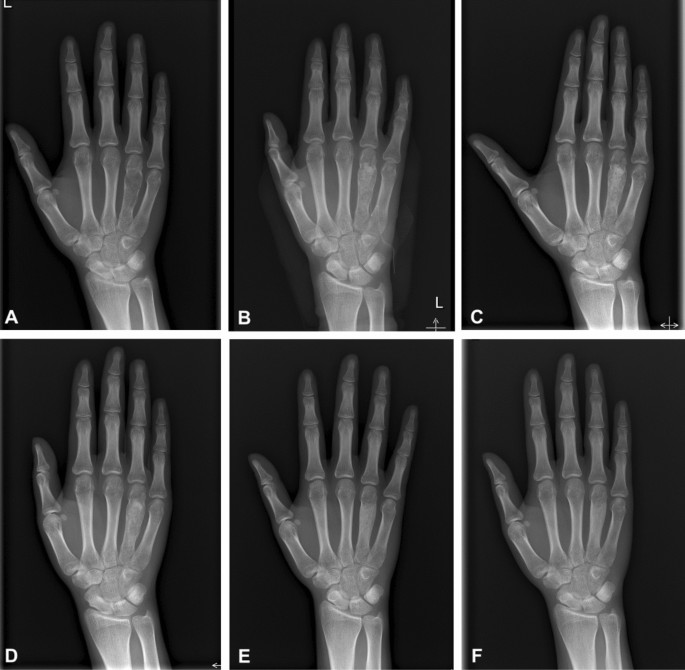

Enchondroma Hand

Enchondroma - Azouz Hand SurgeryAzouz Hand Surgery Enchondromas - Pathology - Orthobullets LearningRadiology- Enchondroma Enchondroma-of-hand LearningRadiology- Enchondroma Enchondroma Hand